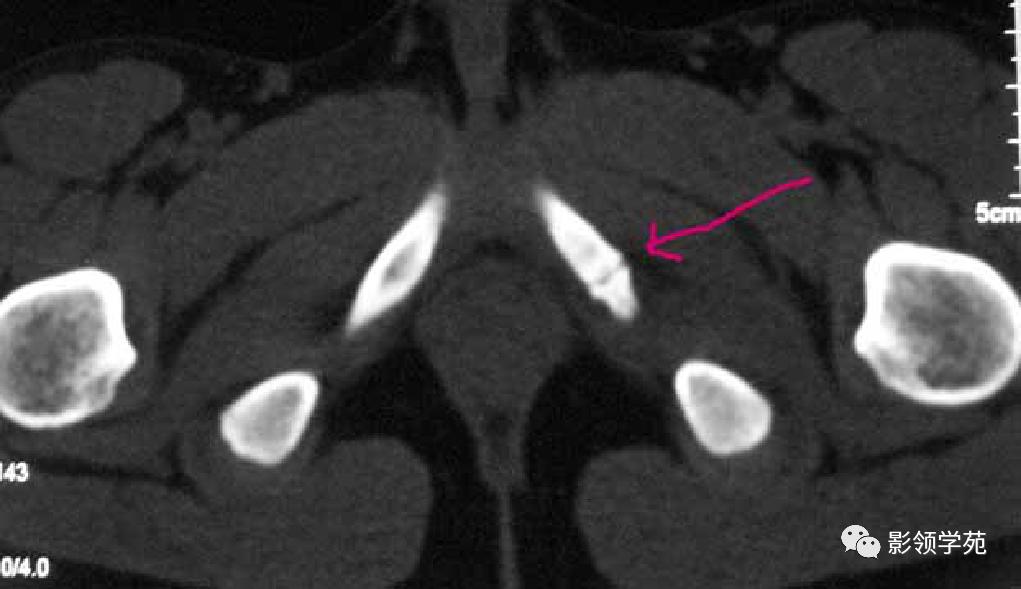

副骨

副骨是由于某一块骨的多个骨化中心在发育过程中没有融合、以致形成多出一块或几块的小骨,也可以是由一个额外的骨化中心发育而来。

永存骨骺、籽骨和副骨的发生与其特有部位及典型特征紧密联系。

常见案例均具有骨块边缘钝圆、骨皮质连续、局部软组织无明显肿胀以及伤后该骨的连续摄片无明显变化等非撕脱性骨折的共同特点。

籽骨、副骨与永存骨骺一般边缘光滑, 周围皮质密度较高, 皮质光整, 附近骨质结构完整, 具有对称性, X线随诊形态及位置不会发生改变, 一般不会引起疼痛。但个别患者由于一些局部肌肉的扭伤而引起副骨的移位, 或由于机械外力的作用使副骨摩擦软组织导致滑囊炎和肌腱炎, 甚至由于长期慢性磨损可与附近正常骨质形成假关节从而产生创伤性关节炎可引起疼痛。而骨折一般具有明确的外伤史, 附近软组织肿胀明显, 疼痛症状明显, 断端锐利, 皮质断裂, 不具有对称性, X 线随诊形态及位置可发生移位。而籽骨、副骨与永存骨骺本身也可在外伤的情况下发生骨折, 但极罕见。